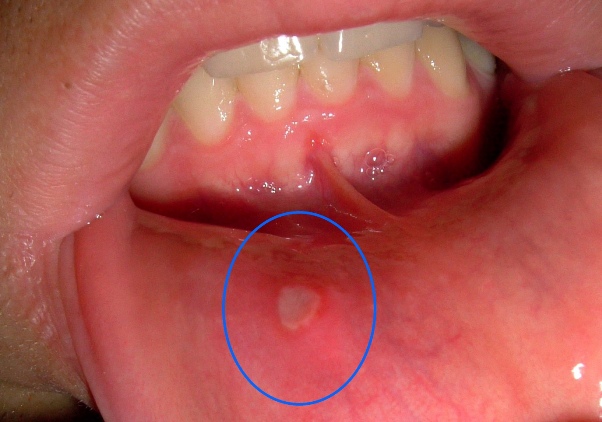

Afte su male ulceracije koje se najčešće pojavljuju na unutrašnjim dijelovima usana, jeziku ili sluznici usne šupljine.

One mogu biti pravi izazov jer otežavaju svakodnevne aktivnosti poput žvakanja hrane, razgovora, pa čak i pijenja vode. Ako ste ikada imali afte, znate da je bol koja prati ovaj problem izuzetno neugodna. Iako većina afti nestaje sama od sebe u nekoliko dana, postoji nekoliko prirodnih metoda koje vam mogu pomoći da ih se brže riješite i ublažite bol.